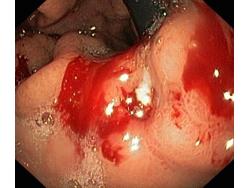

Krwawienie